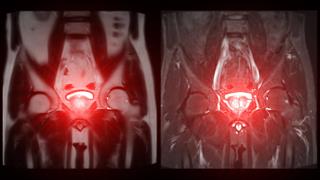

Σημαντική βελτίωση στη διάγνωση του καρκίνου του προστάτη έχει φέρει η πολυπαραμετρική μαγνητική τομογραφία - μία εξελιγμένη εξέταση που απεικονίζει με μη επεμβατικό τρόπο τον προστατικό αδένα, αναδεικνύοντας τα ύποπτα σημεία του.

Η πολυπαραμετρική μαγνητική προστάτη παρέχει λειτουργικές πληροφορίες για τον αδένα, ενώ οι εικόνες της είναι εξαιρετικά λεπτομερείς, εξηγεί. Έτσι αντανακλά τις βιολογικές ιδιότητες του προστατικού ιστού, ανιχνεύοντας με ακρίβεια τις εστίες που είναι ύποπτες για καρκίνο. Επιπλέον, μπορεί να ξεχωρίσει εάν ο προστάτης έχει διογκωθεί από άλλη αιτία (π.χ. από μία λοίμωξη ή από καλοήθη υπερπλασία), βοηθώντας τους ασθενείς να αποφύγουν μια βιοψία την οποία δεν χρειάζονται.

«Η λεπτομέρεια της πολυπαραμετρικής μαγνητικής τομογραφίας είναι τόσο μεγάλη ώστε μας επιτρέπει να ξεχωρίσουμε τον καρκίνο από όγκους, μάζες ή άλλες διαταραχές που επηρεάζουν όργανα και ιστούς γύρω από τον προστάτη (π.χ. ουροδόχος κύστη, ουρήθρα), προκαλώντας παρόμοια συμπτώματα. Επιπλέον μπορεί να μας δείξει και πόσο προχωρημένος είναι ο καρκίνος, απεικονίζοντας αν έχει εξαπλωθεί στους πυελικούς λεμφαδένες ή στα οστά της πυέλου», τονίζει ο κ. Πούλιας.